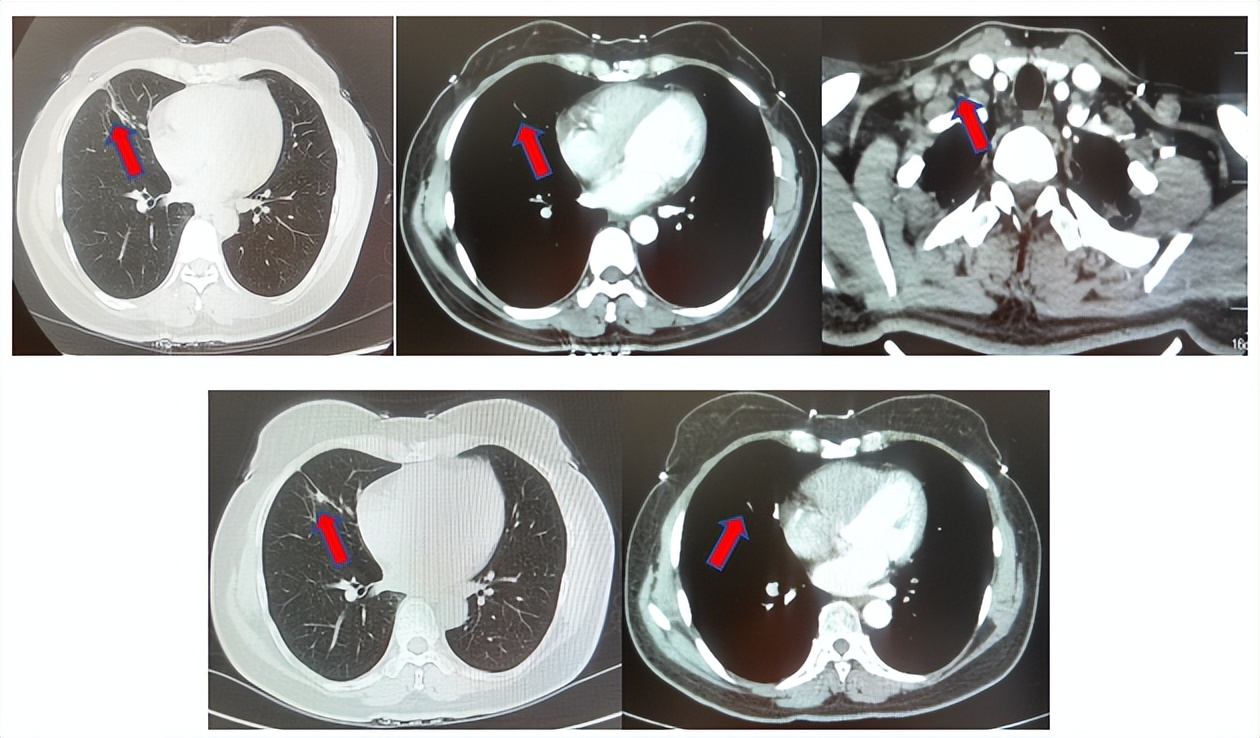

患者进入到二线治疗,该患者再次符合我科“优替德隆对照多西他赛治疗含铂化疗失败的局部晚期或转移性非小细胞肺癌的III期、开放、随机对照临床试验”经随机进入多西他赛组,截止至目前患者已行多西他赛治疗19周期,期间评效为SD(图3),二线无进展生存至今为14个月,患者总生存期截止目前超过92个月(整体治疗过程如图4所示)。

图3:上两图分别展示2024年1月患者一线进展时肺CT肺窗及纵隔窗肺内病灶影像,下两图表示2024年12月患者二线治疗间期评效时肺CT肺窗及纵隔窗肺内病灶影像

2.2影像学检查(图5)

肺+全腹CT增强:右肺中叶肿块,考虑恶性,双肺胸膜下炎症,双侧胸膜局限性增厚,右侧锁骨上淋巴结增大,纵隔淋巴结稍大;

颈部CT增强:右侧锁骨上及右颈部、纵隔多发淋巴结肿大。

图5:上两图分别展示基线时肺CT肺窗及纵隔窗右肺中叶病灶影像,下两图表示基线状态时纵隔淋巴结及锁骨上淋巴结影像。